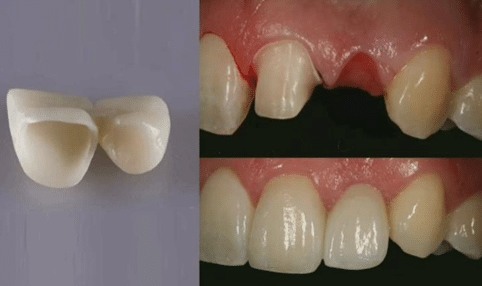

Variante : bridge à ailettes

Pontique placé en latéral.

Deux ailettes métalliques collées sur l’incisive centrale et la canine.

Moyens d’ancrage : préparations partielles.

Le terme de “bridge collé” désigne une approche conservatrice introduite au début des années 1970 par Rochette :

Moyen d’ancrage réduit : ailettes disposées au niveau des faces palatines des dents.

Préparation limitée à l’émail.

Fixation assurée par collage : la prothèse est reliée à l’émail des dents au moyen d’une colle.

Absence totale de rétention mécanique : la stabilité repose exclusivement sur l’adhésion.

Indications du bridge collé

Principalement proposé comme solution temporaire, par exemple en attendant une solution implantaire.

Historique : avec les alliages métalliques, aucun matériau d’assemblage satisfaisant n’était disponible.

Aujourd’hui : les matériaux composites de collage permettent une adhésion suffisante, même avec des ailettes en céramique.

Cas particulier : en présence d’agénésie des incisives latérales, relativement fréquente dans la population, il est possible de proposer un bridge collé en solution définitive, avec des ailettes en céramique.

Agénésie des incisives latérales :

Un traitement orthodontique est nécessaire avant la pose d’implants (généralement à partir de 18 ans).

Un bridge dento-porté provisoire peut alors être placé entre l’incisive centrale et la canine.

Agénésie des incisives latérales :

Un traitement orthodontique est nécessaire avant la pose d’implants (généralement à partir de 18 ans).

Un bridge dento-porté provisoire peut alors être placé entre l’incisive centrale et la canine.